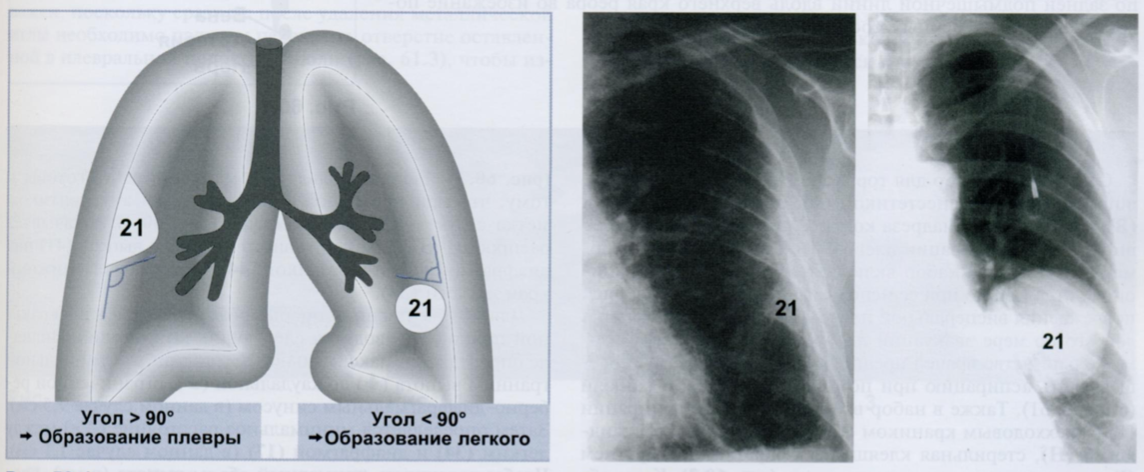

Правило Ленка (схема) помогает установить, исходит ли внутригрудное образование (21) из плевры или легочной ткани.

Образования плевры на боковой стенке грудной клетки, видимые в профиль, образуют с грудной стенкой тупой угол (> 90°) (первая Rx). Это отличает их от внутрилегочных образований, расположенных рядом с плеврой, которые образуют с грудной стенкой острый угол (< 90°) (вторая Rx).